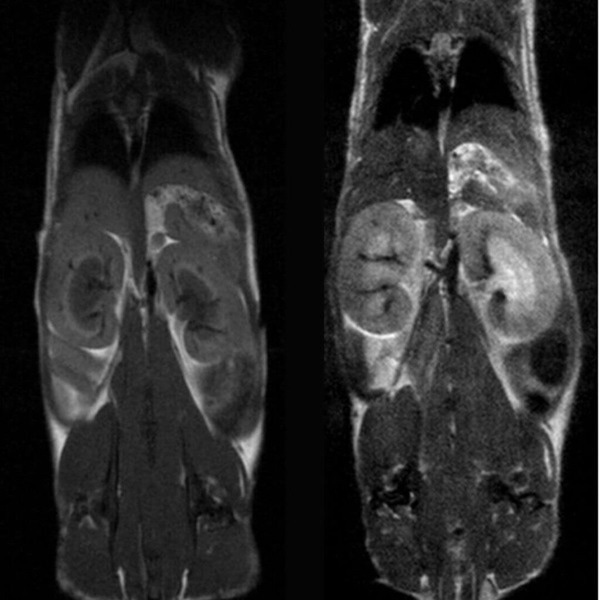

Anatomy & Morphology of mouse abdomen: T1- and T2- weighted scans of wildtype mouse body abdomen.

Anatomy & Morphology of mouse abdomen: T1- and T2- weighted scans of wildtype mouse body abdomen. Image Credit Scintica Instrumentation Inc

T1- and T2- weighted images of Wild-type mouse abdomen.

T1- and T2- weighted images of Wild-type mouse abdomen. Image Credit: Scintica Instrumentation Inc